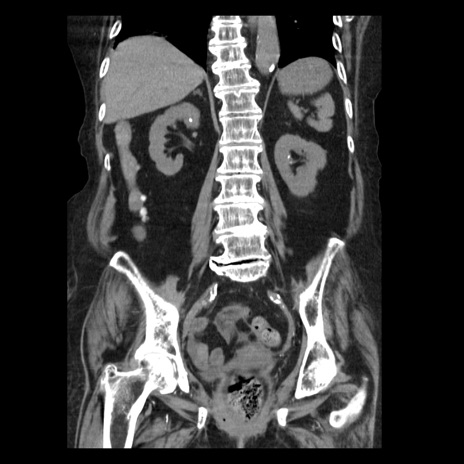

横断像

症例14(冠状断像)

【症例】 90歳代女性

【主訴】 腹痛・嘔吐

【現病歴】今朝から左側腹部痛を認めた。 経過観察していたが、嘔吐を認めたため来院。

【既往歴】 子宮癌術後

【身体所見】 意識清明、BP 127/54mmHg、P 98bpm Sp02 95%(RA)、BT 35.8°C、腹部平坦・軟腸ぜん動音聴取良好、右下腹部圧痛(+) 反跳痛なし

【データ】WBC 9800、CRP 0.46